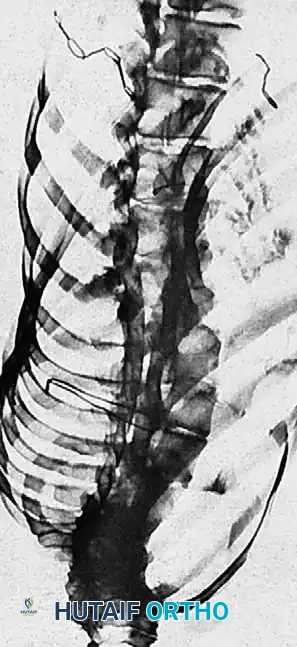

To determine curve flexibility and plan surgical fusion levels, dynamic imaging is required. Supine lateral bending films are standard for assessing the structural nature of the curves.

Fig. 16: Supine lateral bending radiographs demonstrating curve flexibility.

Fig. 17: Push-prone or traction radiographs may be utilized for severe, rigid curves >70 degrees to assess maximum correctability.